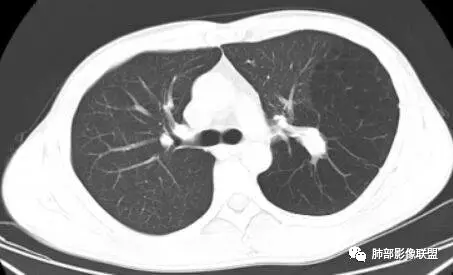

小强:

右上肺孤立性肿块性影,形态规则,边界清,密度25HU左右,没有点状钙化样密度,未见明确强化,周围可见条索,内缘肺透过度增强,有一副裂发育,考虑发育异常,支气管囊肿,CT值略高考虑合并感染;支气管闭锁,邻近未见明确支气管通行可排除;错构瘤,无强化应该是软骨型错构瘤,但是钙化太少,也可以排除;肿瘤,无强化可基本排除;结核球,不出除外

一切∮随缘:

右肺实性结节,形态欠规则,边缘光滑,彭隆,分叶,近端支气管未见显示,可能堵塞,平扫密度均匀,增强扫描,可见贴边血管,实性轻度强化,肿瘤标志物无明显增高,考虑支气管囊肿,错构瘤,

周太狼:

中年男性,右上肺类圆形肿块影,边缘膨隆,无明显分叶毛刺,内可见点状钙化,肿块整体密度较低,增强CT值才25HU左右(说明强化不明显或根本没有强化),周围可见少许斑片索条影,考虑良性病变,首选支气管囊肿,鉴别错构瘤。

滴水海:

看着血管被推移,张力大,应该是无强化,良性病变,支气管闭锁一般周围肺气肿明显,倾向支气管囊肿,鉴别畸胎瘤,CCAM